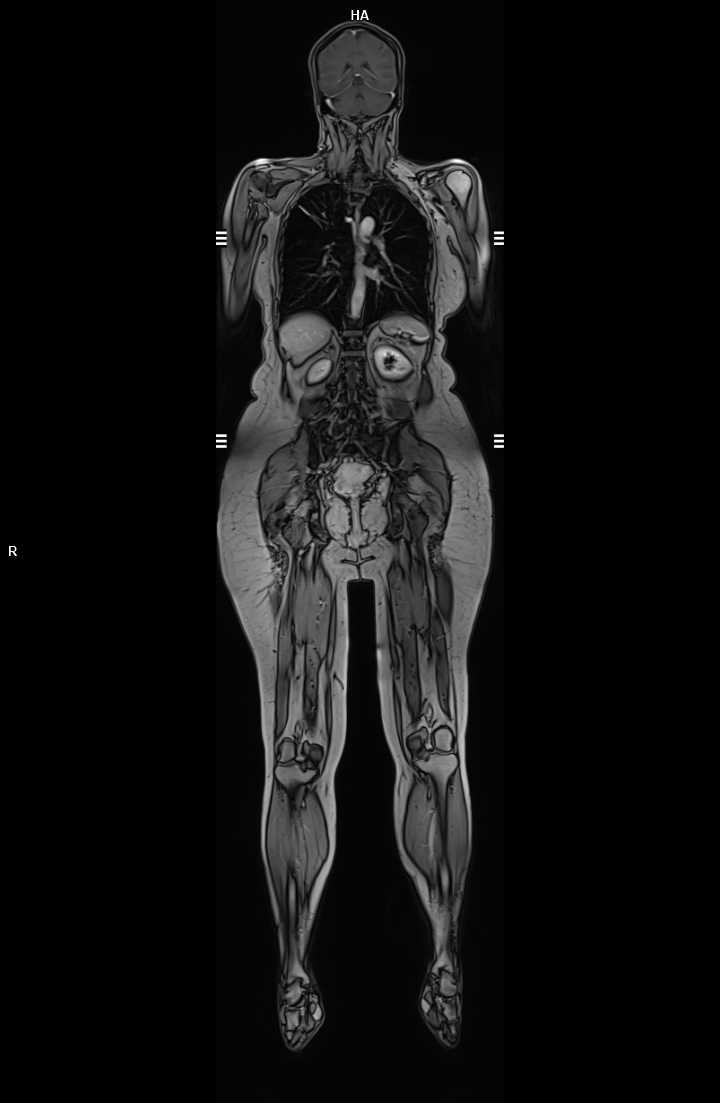

• 3 TESLA MR ÇEKİM GÖRÜNTÜLERİ

3 Tesla MR Çekim Görüntüleri

• 3 Tesla MR Çekim Görüntüleri